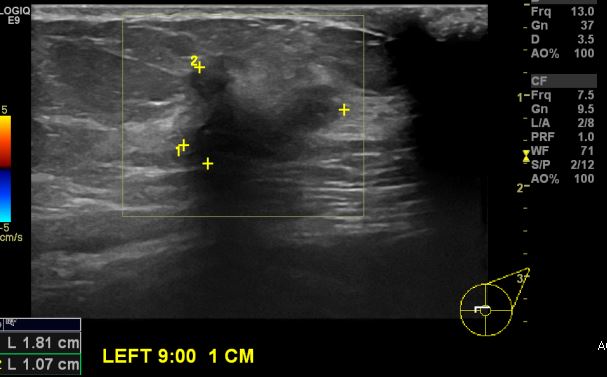

상기환자 좌측 만져지는 멍우리로 내원하신 70대 여성분으로  좌측 9시 방향 1cm

떨어진 거리의 으심스러운 혹 조직검사 시행하여 좌측 침윤성 유관암 진단 되었습니다.